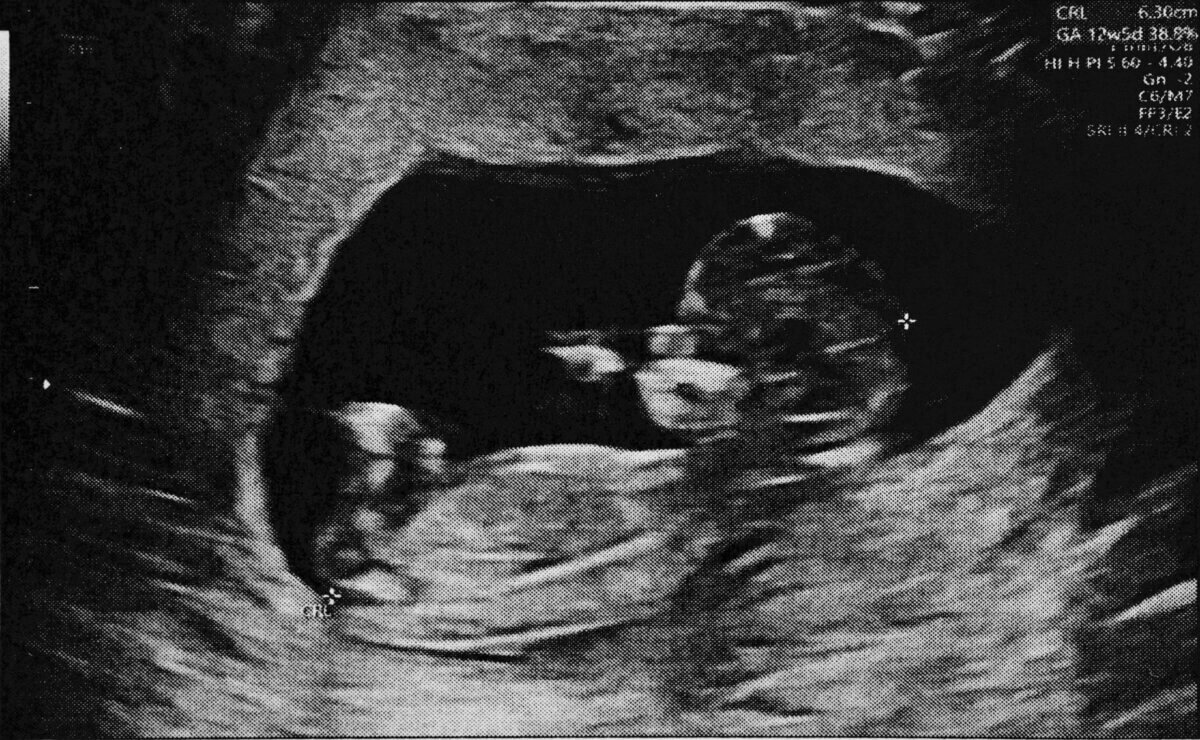

Researchers at several Mexican universities and medical centers studied 37 pregnant women in their third trimester of pregnancy. They wanted to understand exactly how classical music might influence these delicate heart patterns in developing babies.

Starting with 100 pregnant volunteers, the research team ultimately focused on 37 participants whose fetal heart recordings were clear enough for detailed analysis. Getting precise measurements of fetal heartbeats isn’t easy. The signals must be very clear and consistent to measure the tiny variations between beats. Many recordings had too much interference or gaps to be reliable.